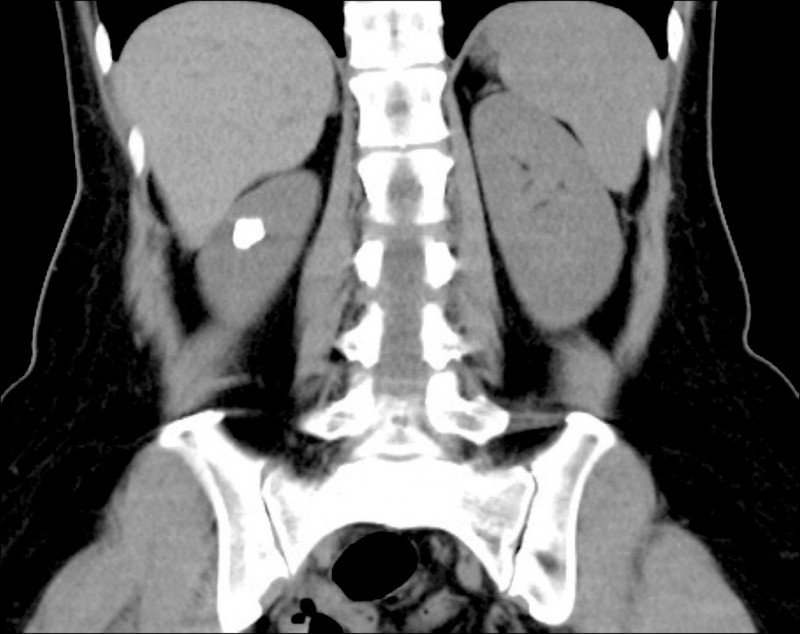

50歲田女士天生患有腎盞憩室並伴隨結石,近期頻繁泌尿道感染,嚴重影響生活品質,轉至大醫院檢查發現,田女士左側腎臟內約有1.5公分的結石群嵌在腎盞憩室中,而憩室與正常腎盞之間的通道僅不到1毫米,導致尿液排出不良並形成結石。

醫師採取雷射切開並擴大憩室的通道,接著以「負壓吸引鞘與軟式輸尿管鏡碎石手術」將結石擊碎,並同步吸出,放置雙J導管維持通暢直至傷口定型後取出,解決多年來的結石與反覆感染問題。

針對腎盞憩室結石的治療,傳統多採用經皮穿腎取石術(PCNL),需從背部切開傷口,並以粗度約1公分的導管穿刺進入腎臟取石,傷口較大、且因腎臟血流旺盛,出血風險相對較高,隨醫療技術進步,目前小於2-3公分的腎盞憩室結石可透過「負壓吸引鞘與軟式輸尿管鏡碎石手術」治療,是利用極細的軟式輸尿管鏡由尿道進入腎臟,配合高能雷射將結石擊碎並吸出,再視情況切開並擴大憩室通道洞口、避免尿液淤積,造成結石復發。